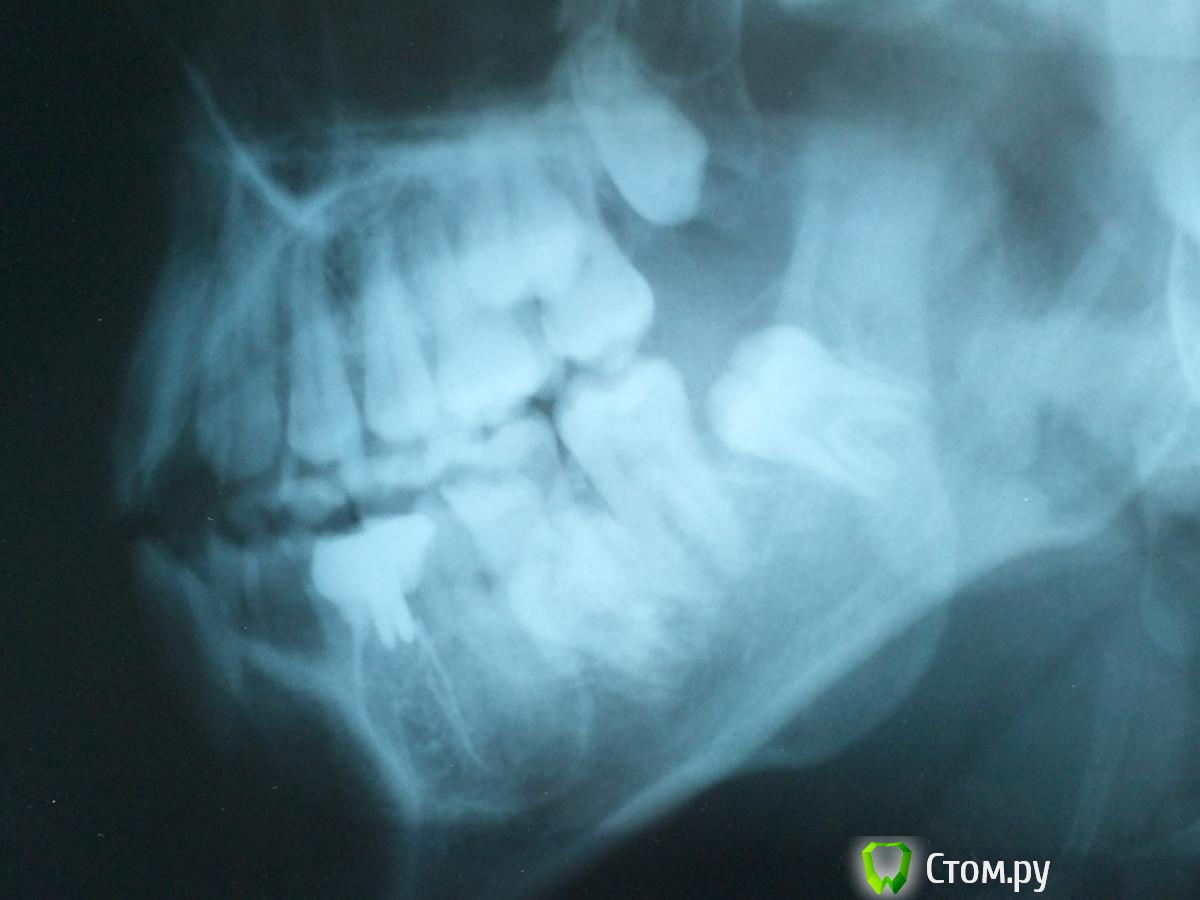

Александр1996 Опубликовано 29 мая, 2014 Автор Поделиться Опубликовано 29 мая, 2014 Что бы это могло быть ? Вот только вернулся от другого врача , решили мне вскрыть 35 зуб ( самый больнющий) Поставили 3 укола не морозило , сверлили и чистили канал считай на живую , вышло немного жидкости и сукровица ,сейчас уже такая боль не ощущается , канал оставили открытым , полоскать сказали чтобы прочистить его , вот Вот ещё 1 снимок тоже 5 зуба Ссылка на комментарий

faity Опубликовано 30 мая, 2014 Поделиться Опубликовано 30 мая, 2014 Вот ещё 1 снимок тоже 5 зуба удалять зубы мудрости, пролечивать 3.5, делать КТ, похоже на ростовую кисту, все лечится если лечить Ссылка на комментарий